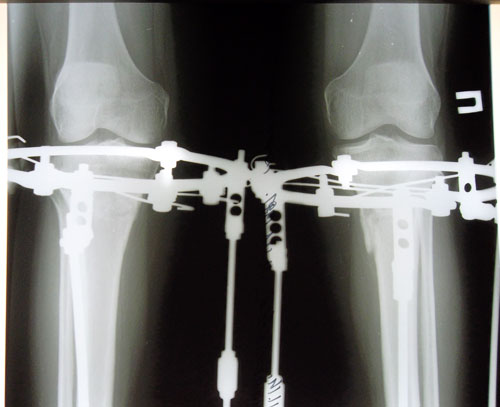

Рентген перед снятием аппаратов.

Вложения

SAM_9259.JPG